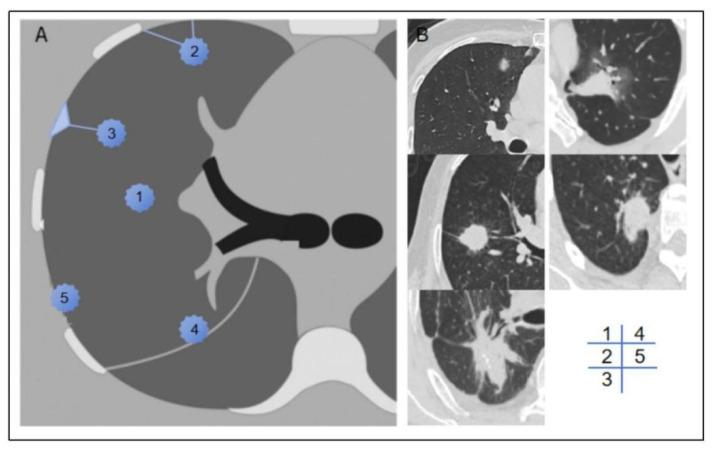

The preoperative identification of occult pleural metastasis (OPM) in lung cancer remains a crucial clinical challenge. This study aimed to develop and validate a predictive model that integrates clinical information with chest CT radiomic features to preoperatively identify patients at risk of OPM.

METHODS

This study included 50 patients diagnosed with OPM during surgery as the positive training cohort and an equal number of nonmetastatic patients as the negative control cohort. Using least absolute shrinkage and selection operator (LASSO) logistic regression, we identified key radiomic features and calculated radiomic scores. A predictive nomogram was developed by combining clinical characteristics and radiomic scores, which was subsequently validated with data from an additional 545 patients across three medical centers.

RESULTS

Univariate and multivariate logistic regression analyses revealed that carcinoembryonic antigen (CEA), the neutrophil-to-lymphocyte ratio (NLR), the clinical T stage, and the tumor-pleural relationship were significant clinical predictors. The clinical model alone achieved an area under the curve (AUC) of 0.761. The optimal integrated model, which combined radiomic scores from the volume of interest (VOI) with the CEA and NLR, demonstrated an improved predictive performance, with AUCs of 0.890 in the training cohort and 0.855 in the validation cohort.

CONCLUSIONS

Radiomic features derived from CT scans show significant promise in identifying patients with lung cancer at risk of OPM. The nomogram developed in this study, which integrates CEA, the NLR, and radiomic tumor area scores, enhances the precision of preoperative OPM prediction and provides a valuable tool for clinical decision-making.